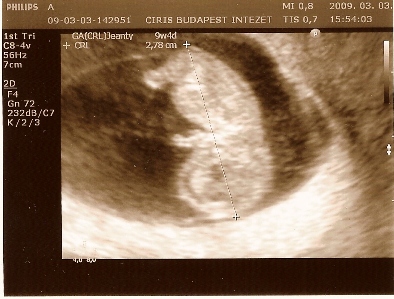

Tegnap volt az ultrahang, és marha jó volt. :D Igaz két órát kellett várnom, mert ISO ellenőrök voltak egész nap bent a C-ben, és már mindenkinek az agyára mentek. V doki megcsúszott miattuk, és mire beértünk, akkor ment be műteni. Hát nem irigylem a lányt sem, aki egész nap a műtétre várt, már biztos túl akart lenni rajta.

Viszont március 1-gyel árat emeltek. Majd nézzetek utána, azt nem tudom, hogy fent az oldalon a régi vagy már az új árak vannak. 19 ezret fizettünk az ultrahangért.

A kis Tökéleteske nagyon jól van. Már 27 mm-s. Doki felébresztette az ultrahangkor és csápolt kind a két kezével és lábával. Nagyon édes volt. Bent táncolt anya hasában. Ezen a téren rám hasonlít. Akkora pocakja van, úgy néz ki, mint egy jóllakott napközis. Ebben meg apukájára hasonlít. :-) A szíve nagyon hangosan vert.

Megpróbálom a képeket is feltenni. Az egyik képen csak egy talp látszódik. Tartozik hozzá gyerek is. :-)